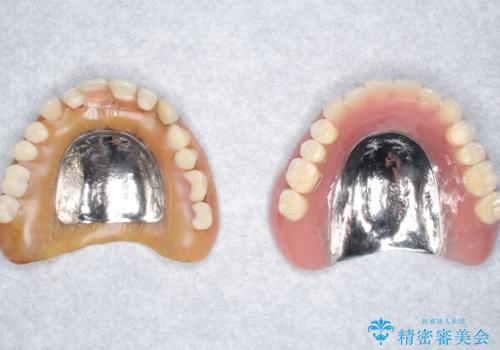

患者様のご希望により、上顎金属床義歯の新製を行いました。

適合を良くするため、咬座印象も行いました。